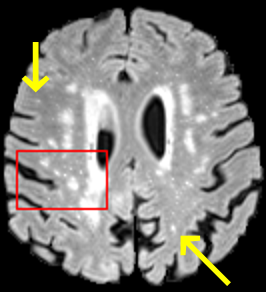

To test the impact of the iterative refinement on YODA’s translation quality, we compared regression and diffusion sampling on the RS data and present additional generation examples in Fig. 6. We observe that diffusion sampling visually resembles the appearance of the acquired images. Regression sampling preserves key anatomical features – the GM/WM boundary, WMHs (Fig. 4), the outline of the pallidum (Fig. 6) – but omits many high-frequency features. To investigate whether iterative refinement during diffusion sampling adds relevant and systematic medical information or only imitates acquisition noise, we performed ExpA sampling, i.e. averaging the output of several ( or ) diffusion trajectories. We observed a gradual loss of high-frequency details when increasing the (see also the supplementary video), indicating that the effect of the iterative refinement is non-systematic. For , the images are visually almost indistinguishable from the initial regression solution (see the supplementary video, and Fig.4 and 6). We directly compared the synthesis results of ExpA () and regression sampling quantitatively and found the differences to be minimal (SSIM: 99.73%, PSNR: 45.30 dB), i.e. diffusion sampling approaches the initial regression solution for a high . The quantitative analysis of the image quality (Tab. 1) showed that diffusion sampling impairs the assessed SSIM and PSNR in comparison to regression sampling for both the in- and external test sets, which we attribute to noise generation (Sec. 3.1). In turn, ExpA averages improved both metrics and, for , performed mostly on par with the regression solution in both test sets in terms of SSIM, while the PSNR in the RS was slightly increased (Tab. 1). However, we observed that ExpA sampling YODA improves the replication of systematic 3D low-frequency image intensity drifts (bias fields) due to the 3D synchronization in 2.5D diffusion sampling. Yet, this apparent advantage did not generalize to the external MBB dataset, as bias fields are MR protocol-specific.

We evaluated the impact of the proposed sampling methods on the performance of the independent, externally trained SHIVA-WMH tool as compared to manual reference labels (Tab. 1). Smoother images (higher or from regression sampling) yielded improved performance over those from diffusion sampling.

To assess the suitability of YODA-generated images for WMH detection independent of segmentation tools, we also calculated the CNR (15) of WMHs. This confirmed that the contrast of WMHs is preserved in the regression images, whereas we noted slightly reduced WMH contrast for diffusion and ExpA-sampled images (Tab. 1).

On the RS data (Tab. 1), regression sampling of YODA significantly outperformed all competing methods both w.r.t. the image quality and – except the ALVR for MADM – downstream WMH segmentation, whereas the DB of Choo et al. [31] achieved an higher WMH CNR.

When analyzing the RS synthesis results (Fig. 4), we noted that most reference methods strive to imitate realistic images, but several artifacts can be observed such as hallucinated WMHs (SynDiff) and salt-and-pepper noise (SynDiff, I2I-Mamba, ResViT).